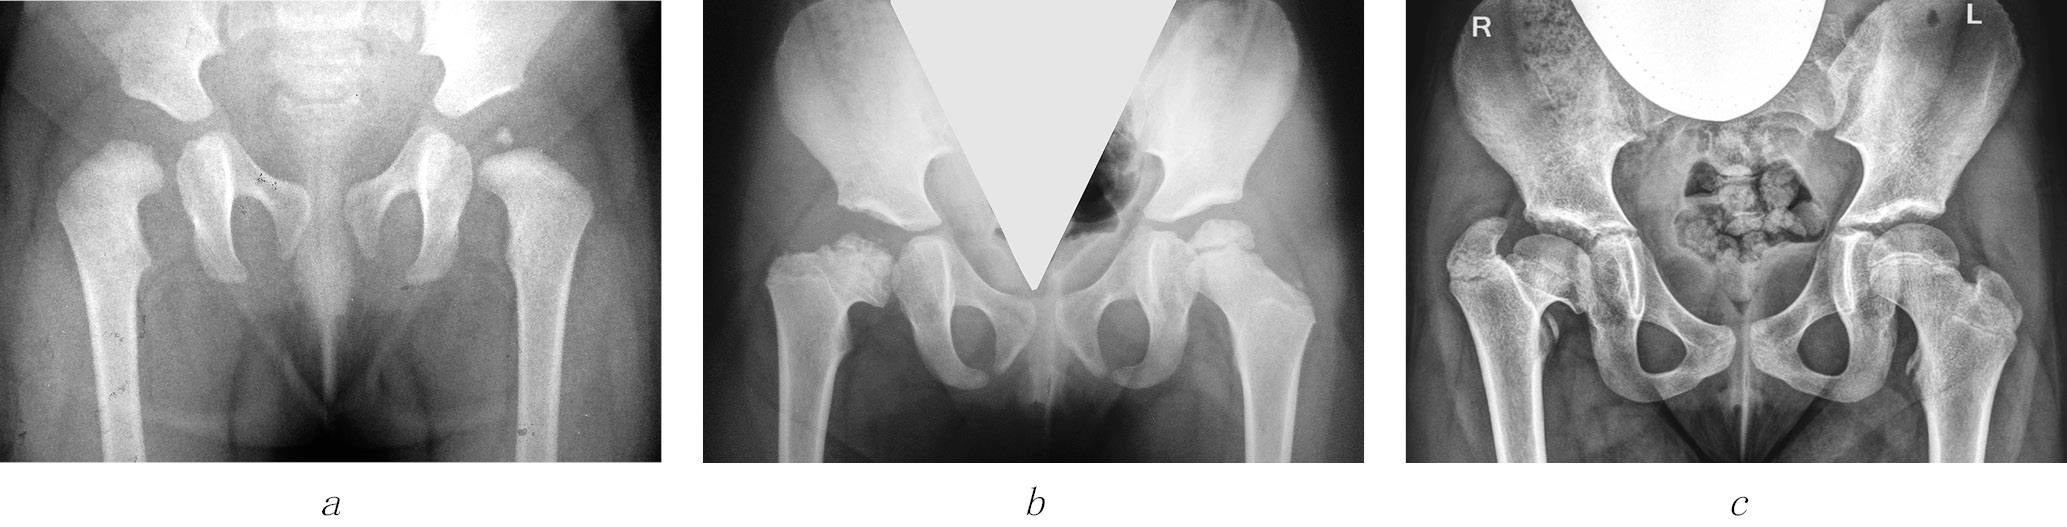

1) последствия ишемического некроза головки бедренной кости как осложнения консервативного лечения при дисплазии тазобедренных суставов и врожденном вывихе бедра —143 (40,9 %) ребенка (рис. 3);

Рис. 3. Рентгенограммы пациентки Ш. Формирование многоплоскостной деформации проксимального отдела бедренной кости с высоким положением большого вертела после перенесенного аваскулярного некроза головки бедренной кости (справа — IV типа, слева — II типа по Kalamchi и MacEwen). В анамнезе — консервативное лечение по поводу врожденного вывиха бедра с двух сторон: а — в возрасте 1 года 2 месяцев; б — в возрасте 3 лет 9 месяцев; в — в возрасте 11 лет

2) последствия гематогенного остеомиелита (септического артрита) — 101 (28,9 %) ребенок. В эту группу также вошли пациенты, перенесшие внутриутробные инфекции и хирургические вмешательства на первом году жизни по поводу врожденных пороков сердца, атрезии пищевода, кишечной непроходимости, трахеопищеводных свищей, осложнившиеся инфекционным поражением тазобедренных суставов (рис. 4);

Рис. 4. Рентгенограммы пациентки Ж., 7 лет. Последствия гематогенного остеомиелита — многоплоскостная деформация проксимального отдела бедренной кости с высоким положением большого вертела слева: а — прямая проекция; б — проекция по Лауэнштейну